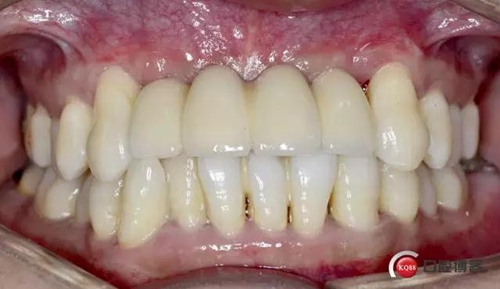

戴牙完成